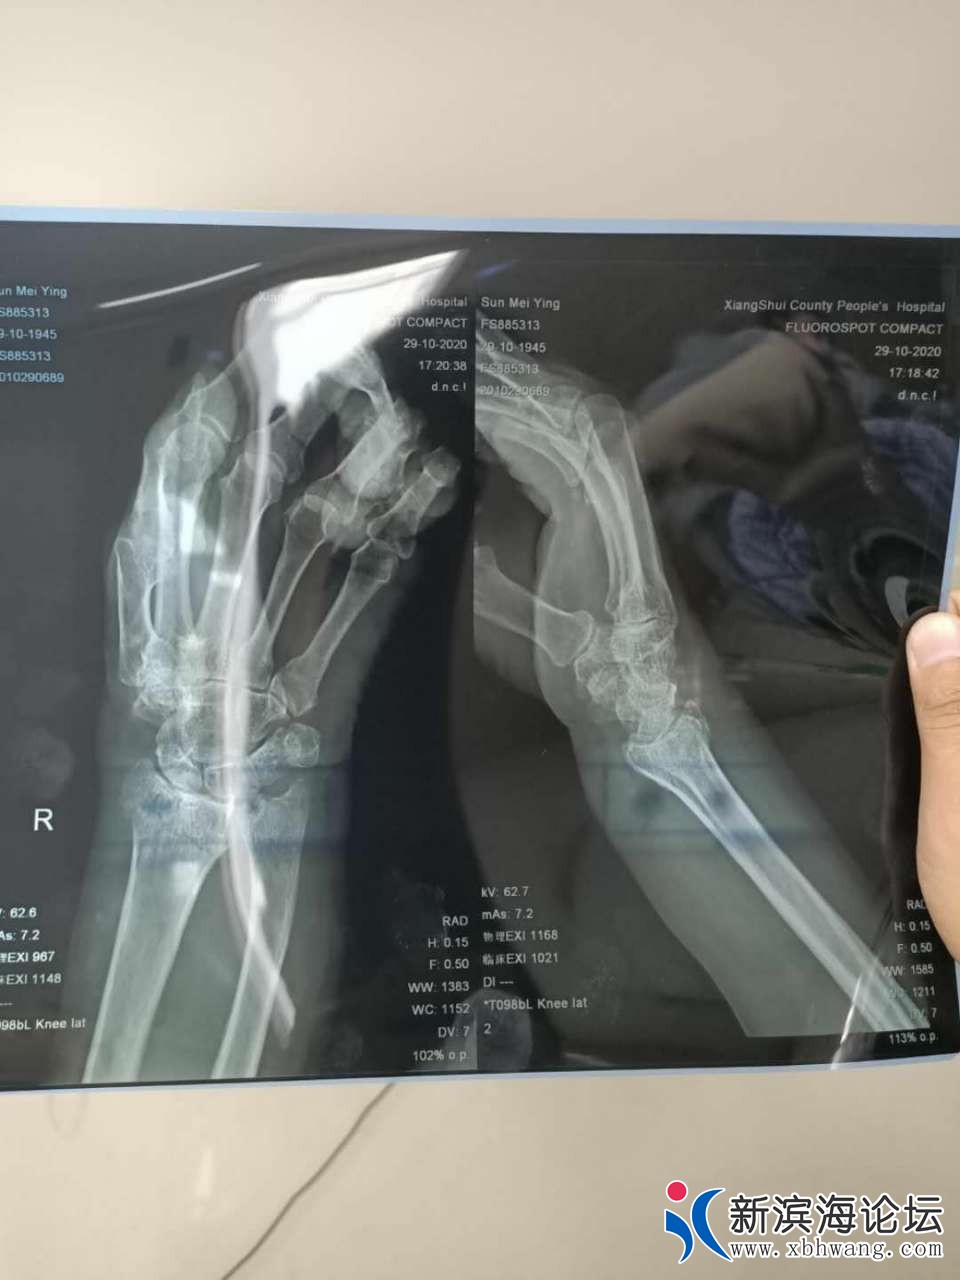

2020年,10月29日,上午8:20左右,南河镇新海村书记暴打陈港镇小港村村民孙梅英老人(75岁女)(老人2015年被确诊为直肠癌花了十几万把老人从死亡边缘拉回来)这一打造成老人右手桡骨骨折,事后书记扬长而去不闻不问,老人右手腕明显鼓起,出现头晕呕吐疼痛难忍,后来老人的家人赶到现场报警,警察让老人自家先去检查,老人要求书记亲自带去检查,一直拖到下午3点才去南河医院,检查右手桡骨骨折,南河医院不接收治疗,让病人去县医院治疗,县院检查结果和南河医院检查结果一样,右手桡骨骨折,这不是新海村书记第一次打人骂人,每年都有被打的人举报都没有用,就在今年春节后2月6号下午4点30分左右,新海村书记的老婆和书记的弟妹打骂老人的二儿媳妇,(嵇海芹40岁精神残疾有残疾证),这一家算不算新海村恶霸,“爆打老人原因是村部承包老人家土地,2017年半年土地费没给,老人也不知道,直到2019年老人的大儿媳妇去银行查了一下,2017年还有半年土地费没打上卡,起初找书记书记不承认,说钱打给你家卡上了,老人家人要求书记一起去银行查看,在证据面前不得不承认,书记当时承诺2019年年底一准打钱,直到2020年10月也没打,老人去找书记要钱不让书记下採桃子,书记就动手打了老人”望有关部门调查。